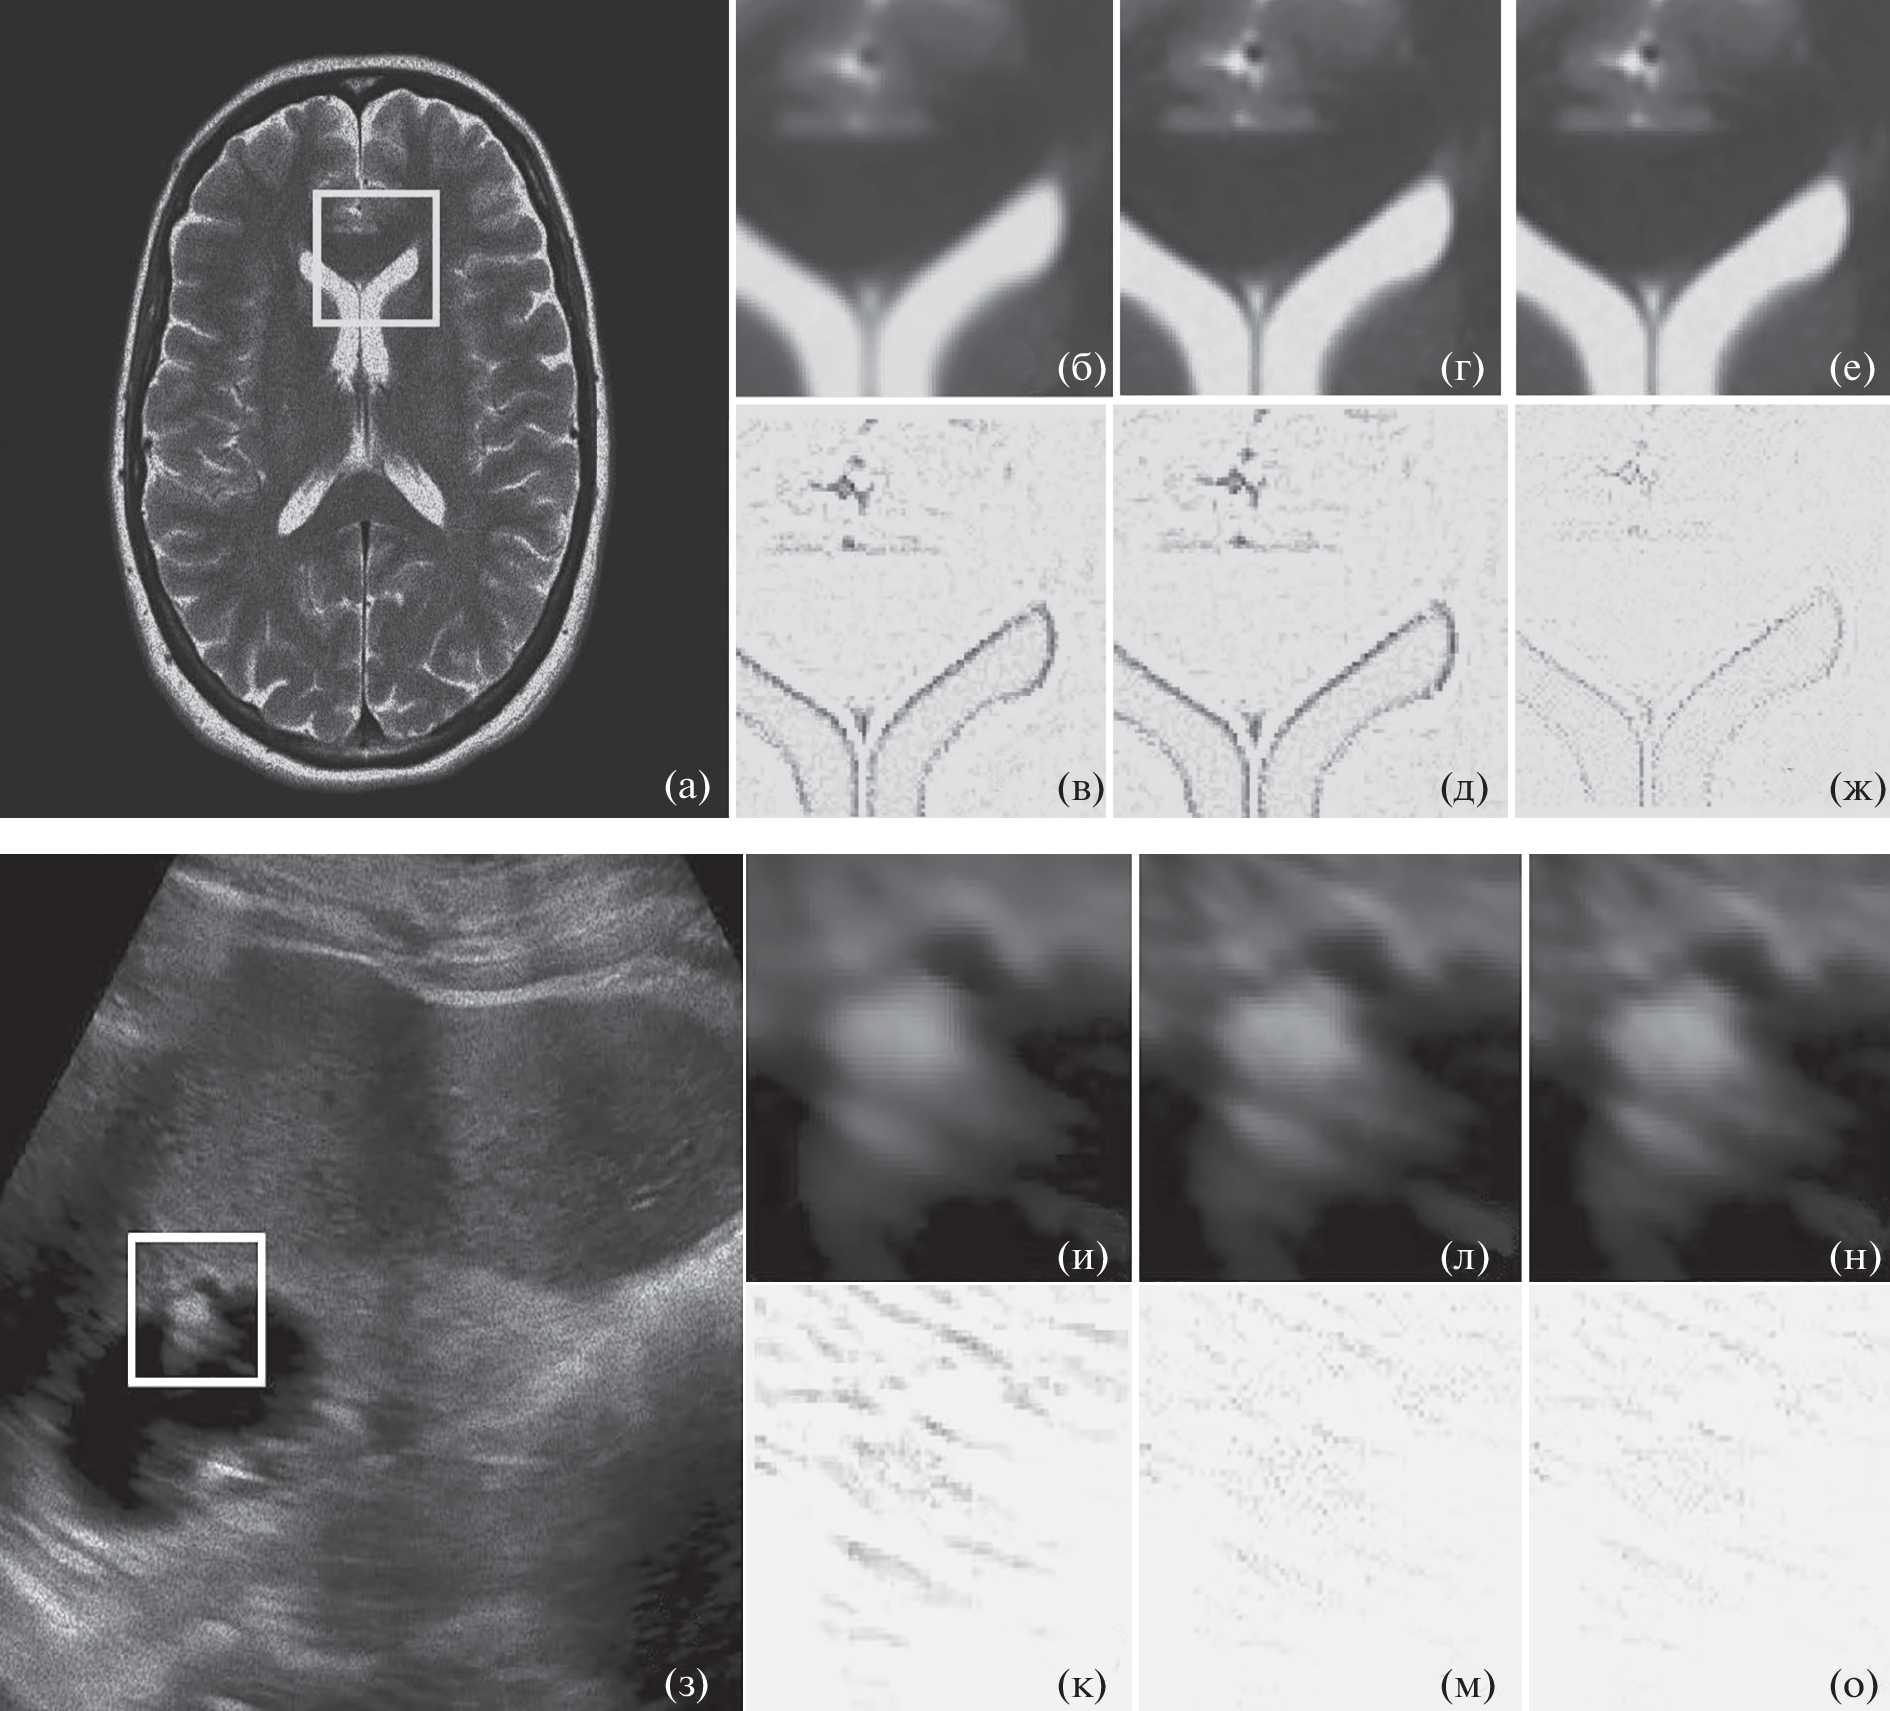

Впервые обоснована и реализована процедура фильтрации ультразвуковых и магнитно-резонансных изображений (УЗИ, МРИ), искаженных мультипликативным (спекл) шумом. Процедура включает следующие этапы: сегментация изображения в ряд однородных регионов, формирование сходных структур в трехмерном пространстве (3D), голоморфное преобразование, пороговая фильтрация изображения в пространстве контуролет преобразования (CLT) с оценкой на основе группирования 3D структур по информационной степени близости и обратное гомоморфное преобразование. Дана физическая интерпретация процедуры фильтрации изображений в условиях спекл шумов и разработана структурная схема подавления шумов. Моделирование предложенного подхода подтвердило преимущество новой процедуры фильтрации изображений в терминах общепризнанных критериев: оценки структурного индекса схожести, пикового отношения сигнал/шум, индекса сохранения контуров и индекса разрешения альфа, а также и при визуальном сравнении профильтрованных изображений.